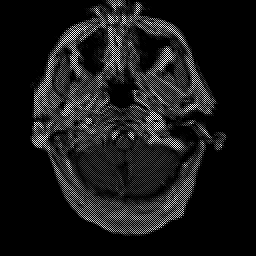

Glioma Overlay -- Slice #2

[Home][Help][Clinical] Slice 2